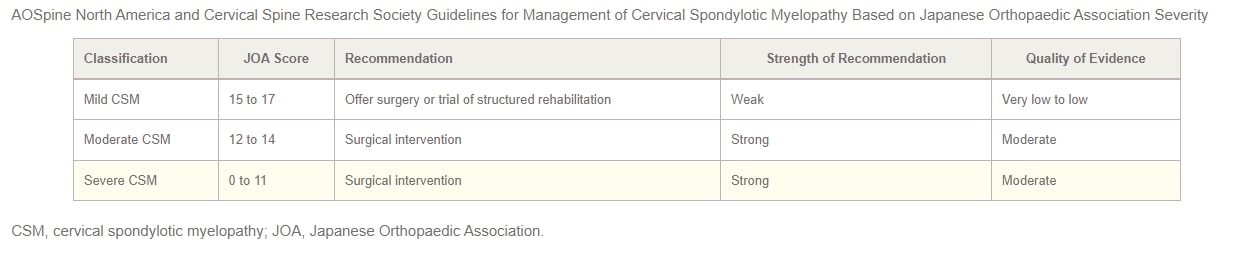

Im Jahr 2017 haben AOSpine North America und die Cervical Spine Research Society (CSRS) haben gemeinsam Leitlinien für die Behandlung von CSM je nach Schweregrad veröffentlicht. Bei Patienten mit leichter CSM sollten die Optionen eines chirurgischen Eingriffs oder eines überwachten Versuchs einer strukturierten Rehabilitation vorgestellt werden. Führt die nichtoperative Behandlung nicht zu einer Verbesserung oder verschlechtert sich der Zustand des Patienten, wird ein chirurgischer Eingriff empfohlen. In Fällen von mittelschwerer bis schwerer CSM wird in den Leitlinien nachdrücklich ein chirurgischer Eingriff empfohlen. Patienten mit einer Kompression des zervikalen Rückenmarks, die keine eindeutigen Anzeichen einer Myelopathie oder Wurzelkompression aufweisen, sollten über die Risiken eines Fortschreitens der Erkrankung beraten und über die Symptome aufgeklärt werden, auf die sie achten sollten, sowie eine regelmäßige klinische Überwachung erhalten.

Schließlich schlagen die Autoren vor, bei Patienten, die eine Kompression des zervikalen Rückenmarks mit Anzeichen einer Radikulopathie aufweisen, entweder eine chirurgische Behandlung oder eine strukturierte Rehabilitation mit enger Nachsorge in Betracht zu ziehen. Die Praxisleitlinien 2017 für die Behandlung von CSM, die nach Schweregrad geschichtet sind, werden in der folgenden Tabelle zusammengefasst: